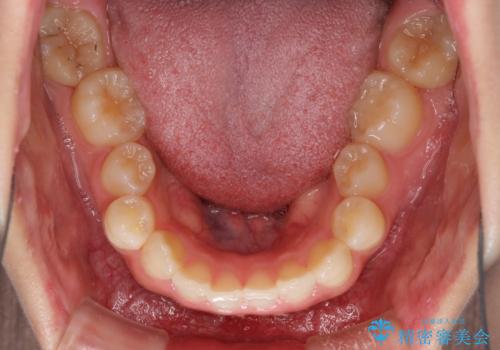

八重歯を改善 目立たないワイヤー装置での矯正治療

- 矯正装置

- 審美装置

- 八重歯を気にして来院された患者様です。

本来であれば八重歯の隣後方の歯を抜歯するのですが、その後ろの歯が乳歯であり後続永久歯もなかったため、乳歯を抜去することとしました。

前から5番目の乳歯は、後続永久歯である小臼歯と比べて幅径が大きいため、移動に時間がかかりましたが、きれいに仕上げることができました。